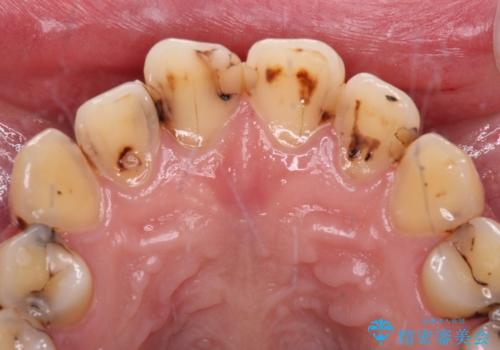

むし歯だらけの前歯をオールセラミッククラウンできれいに

- 上下前歯や奥歯の虫歯治療を希望して来院された患者様です。

全顎的にむし歯が多く、根管治療の必要奥歯や、審美的に気になっている前歯を中心にオールセラミッククラウンにて補綴治療を行うこととしました。